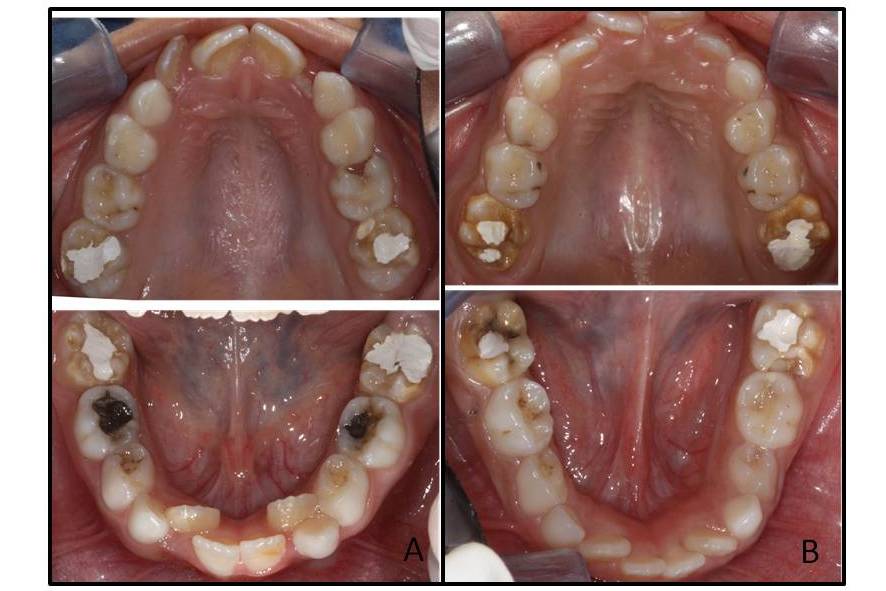

Molar-incisor hypomineralisation is a qualitative defect of dental tissue of systemic origin affecting one or more permanent first molars and sometimes the permanent incisors as well. There are still no conclusive data on the aetiology of this hypomineralisation, however, systemic factors such as respiratory diseases and prenatal and perinatal complications are regarded as possible causes. The objective is to present three clinical cases of twins, one Monozygotic Twins , and two Dizygotic Twins with molar-incisor hypomineralisation, besides showing evidence of its manifestation as well as clinical the characteristics and aetiological factors involved. The clinical findings involving twins show that ameloblasts are specifically affected in their developmental phase, which includes a number of factors although prenatal and perinatal complications not decisive in the development of molar-incisor hypomineralization and suggest a possible genetic susceptibility to the disease. Prospective observational studies using a population sample containing data on the last three months of gestation to the eruption of permanent teeth are needed to confirm the cause-effect relationships.